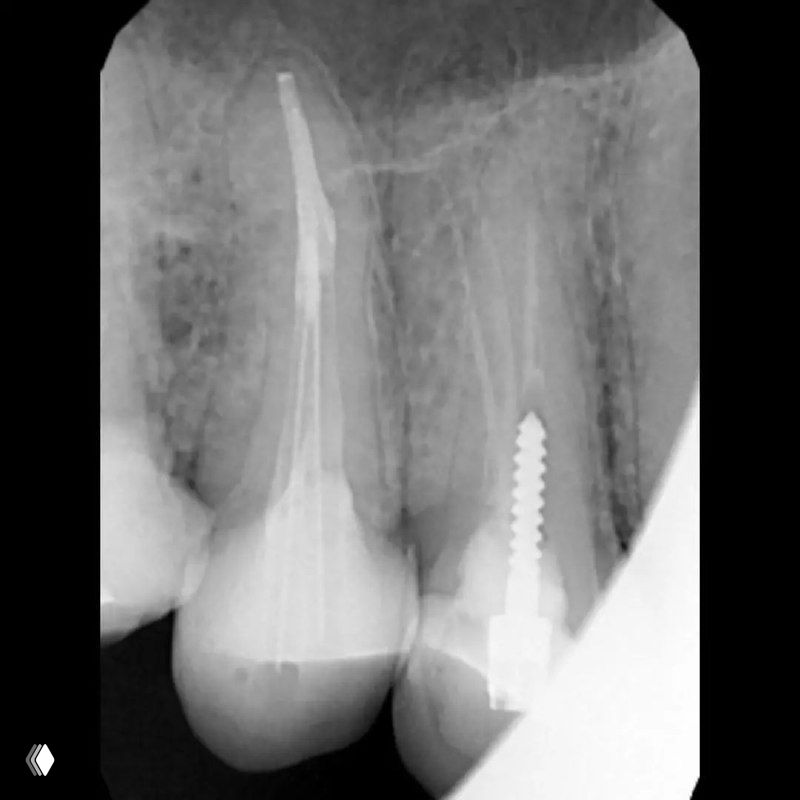

Распространенность: 1 премоляр вч - 3.2%, 2 премоляр вч - 0.4%

На что обратить внимание:

- классическую овальную полость доступа нужно немного расширить в области щёчных каналов в мезио-дистальном направлении

- проводить аккуратное расширение щёчных каналов, так как в области данных корней очень мало дентина (в моём случае расширение 25.04)

- аккуратно латералить без лишнего давления, а для вертикалки использовать самые тонкие плаггеры. А в идеале сделать гибрид.